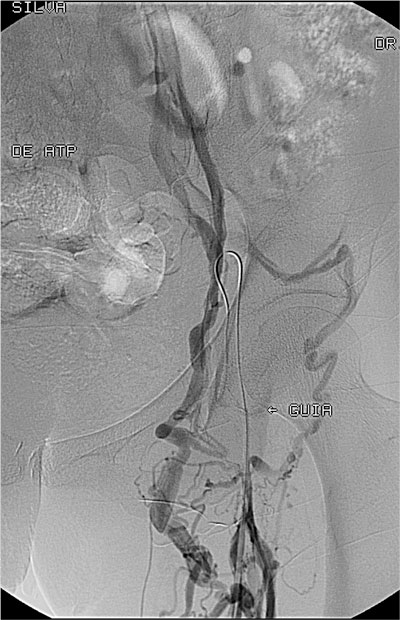

Paciente feminino, 50 anos, portadora de insuficiencia renal terminal em tratamento em outra instituição, já com fibrose peritoneal e com múltiplas confecções de fístulas arteriovenosas nos membros superiores sendo a última fístula um enxerto bráquio-jugular direito pois a paciente apresentava oclusão das veias subclávias. Tal enxerto arteriovenoso havia trombosado há 5 dias e não ocorreu sucesso na tentativa de trombectomia cirúrgica. Sem realizar diálise a paciente apresentava sinais de uremia (confisão mental e sonolência), anasarca e tinha potássio de 8.0mg/dl quando foi solicitado nossa avaliação nesta outra instituição. Encaminhado a paciente para sala de ultrassonografia onde foi avaliado as veias jugulares, subclávias e femorais, todas mostraram-se ocluídas. Em virtude da urgência dialítica foi implantado um cateter de duplo lúmen na veia poplítea direita guiado por ultrassonografia. Foi realizado hemodiálise por três dias consecutivos, sendo alcançado fluxo de 150 ml/min. Houve melhora clínica e dos níveis urêmicos e de potássio. A paciente foi então transferida para nossa instituição onde foi submetida à flebografia dos membros superiores, não ocorrendo opacificação das veias axilares, subclávias e veia cava superior. Realizado tentativa de recanalizacão da veia femoral direita sem sucesso. Optado pelo implante translombar de cateter de duplo lúmen tipo permcath. O procedimento transcorreu sem intercorrências e a paciente teve alta no dia seguinte. Após 9 meses de acompanhamento a paciente apresentou infecção do cateter sendo trocado por um novo cateter via translombar.